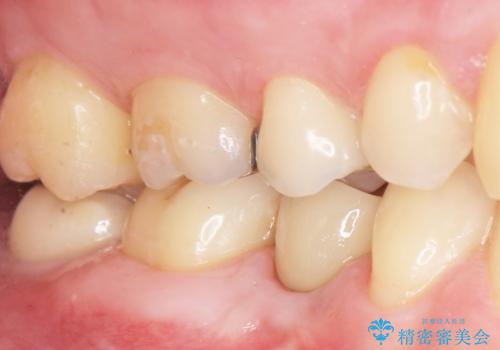

予算を抑えてしっかりとしたインプラント治療 30代男性

- 奥歯(右下5)のインプラントをご希望し来院された患者様です。

なるべく低予算でとのご希望により、アルファタイトインプラント(保証期間:3年)による治療を行いました。

自然な仕上がりと咬み心地に喜んで下さいました。

「低予算でしっかりした治療を受けることができた」とご満足頂けました。

インプラントの種類:アルファタイト

クラウンの種類:オールセラミッククラウン スタンダード